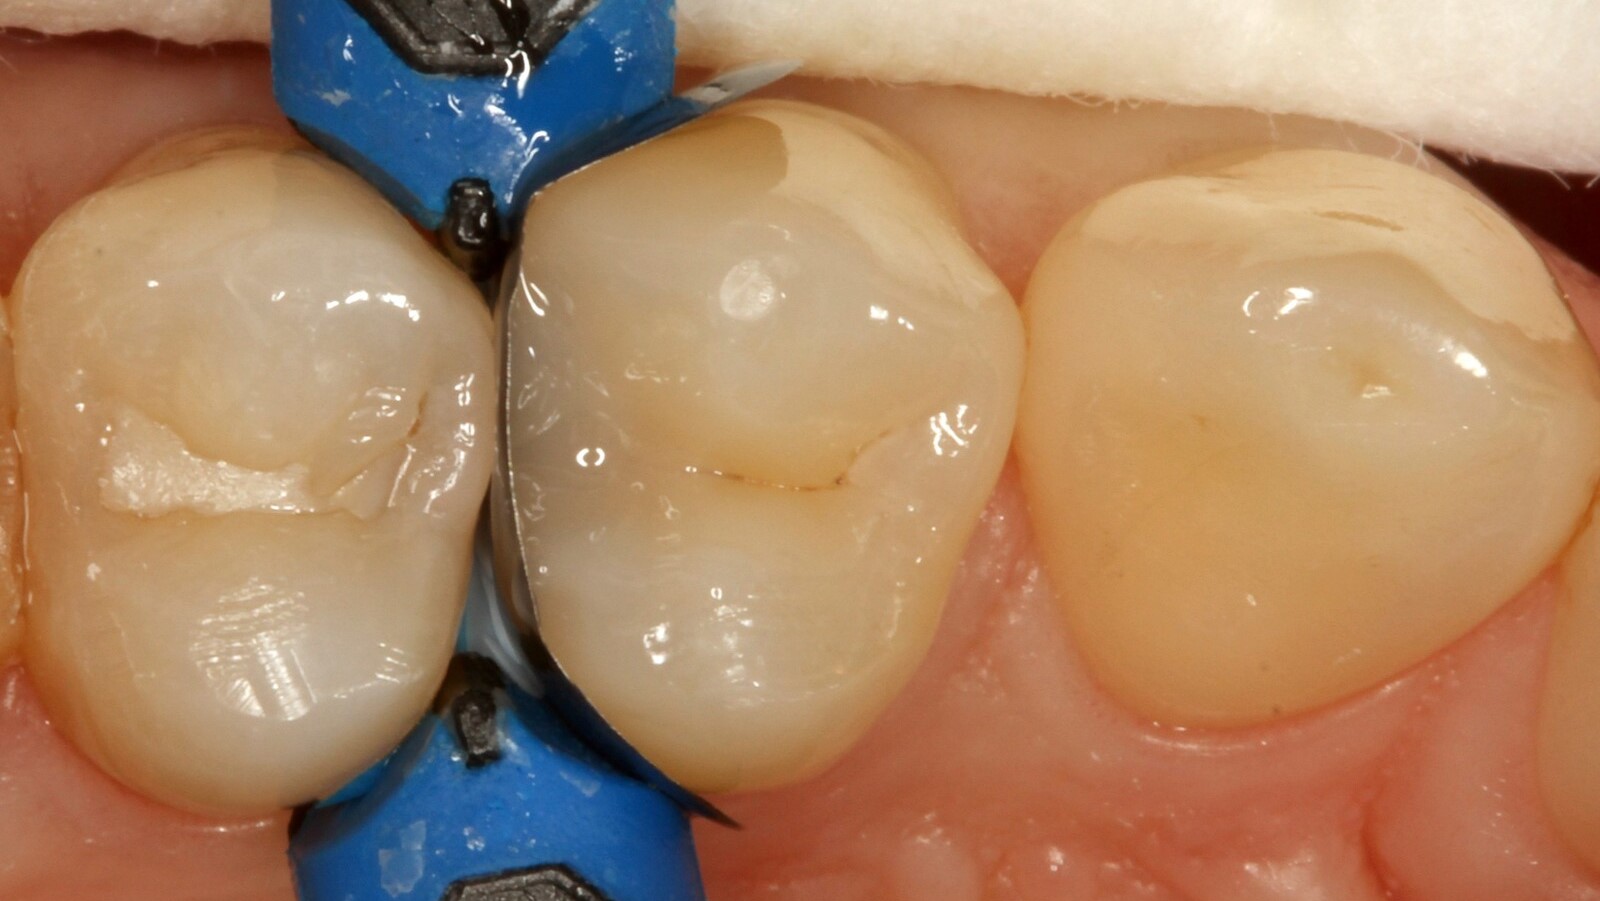

Le professeur Ernst a d'abord identifié les caries non visibles et a ouvert la lésion carieuse pour montrer le problème au patient (Fig. 1-2). Il a ensuite excavé la carie, préparé la cavité et placé une matrice sectionnelle (Fig. 3) avant de sceller la cavité avec de l'adhésif (Fig. 4). En une seule étape, il a rempli la cavité avec Venus Bulk Flow ONE (Fig. 5). Une fois la restauration terminée, le Pr Ernst l'a polie (Fig. 6) et a pris une radiographie de contrôle, qui montre également l'excellente radiopacité de Venus Bulk Flow ONE (Fig. 7).

Venus Bulk Flow ONE est un nouveau composite qui offre une solution d'obturation en Bulk à teinte unique sans qu'il soit nécessaire de procéder à une stratification supplémentaire. Sa consistance fluide le rend facile à manipuler et ses propriétés d'obturation en Bulk lui permettent d'être utilisé par couches de 4 mm, ce qui en fait le composite idéal pour les dentistes à la recherche d'un processus de restauration rapide et efficace. Il s'adapte également à toutes les teintes de dents, de A1 à D4, garantissant ainsi un aspect naturel et homogène.